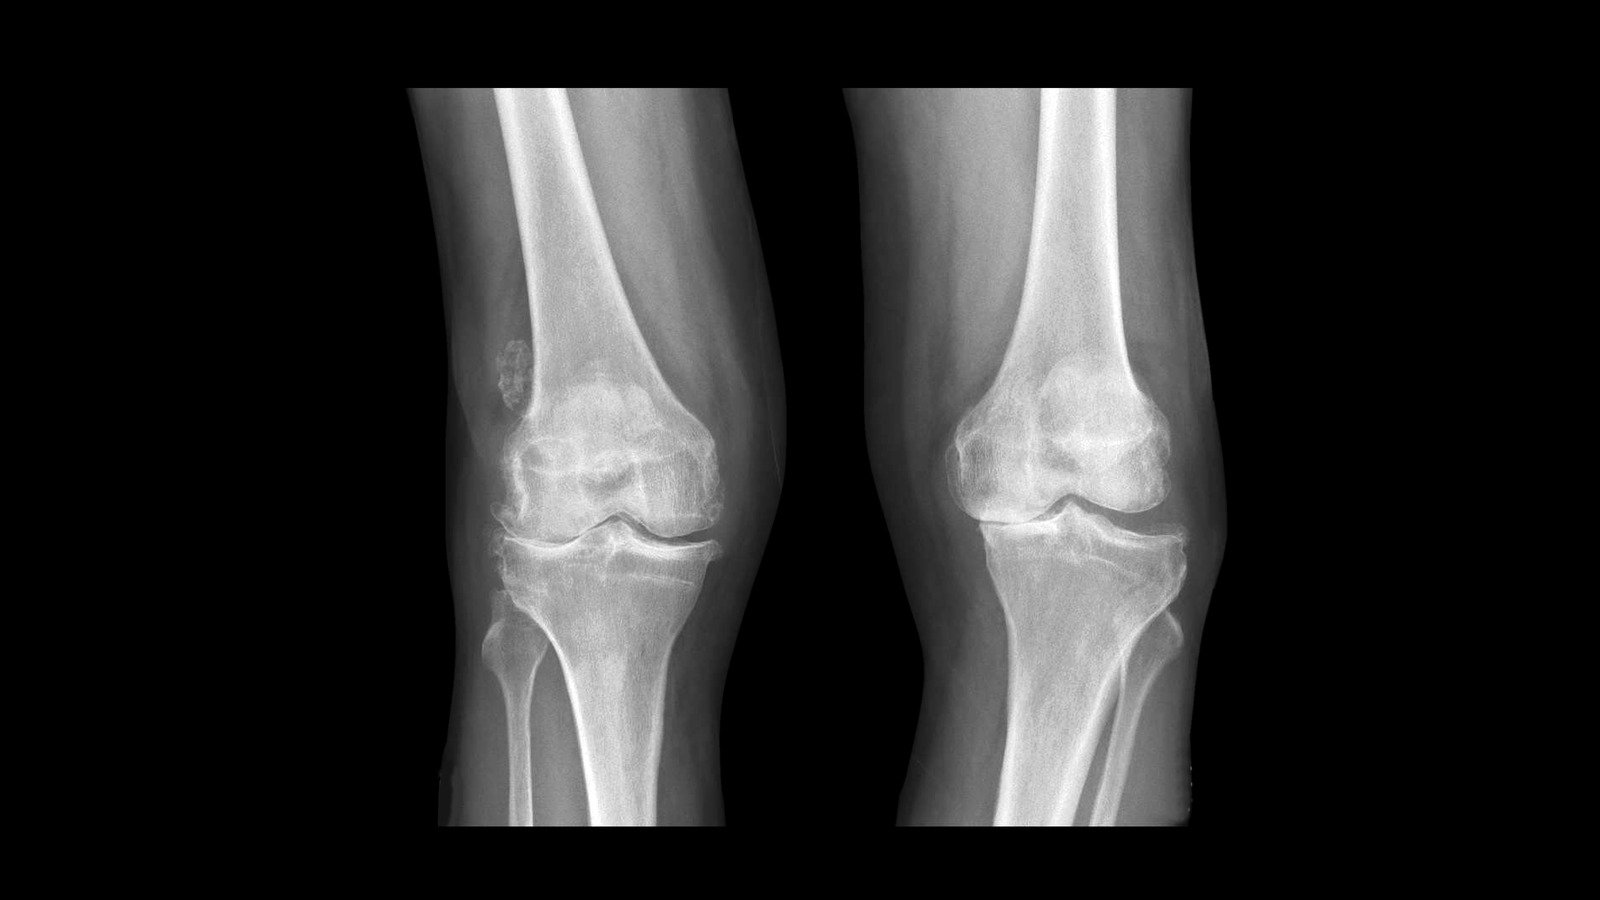

X-ray 검사: 관절 간격이 좁아지거나 연골 손상이 보일 수 있습니다.

MRI 검사: 연골 및 인대 손상을 보다 정밀하게 분석합니다.